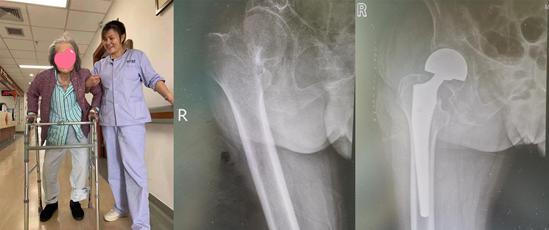

▲92岁老人股骨颈骨折,进行半髋关节置换术治疗后,恢复行动能力

▲93岁老人和95岁老人股骨转子间粉碎性骨折,进行“半髋关节置换术+钛缆内固定”后,重新恢复行动能力